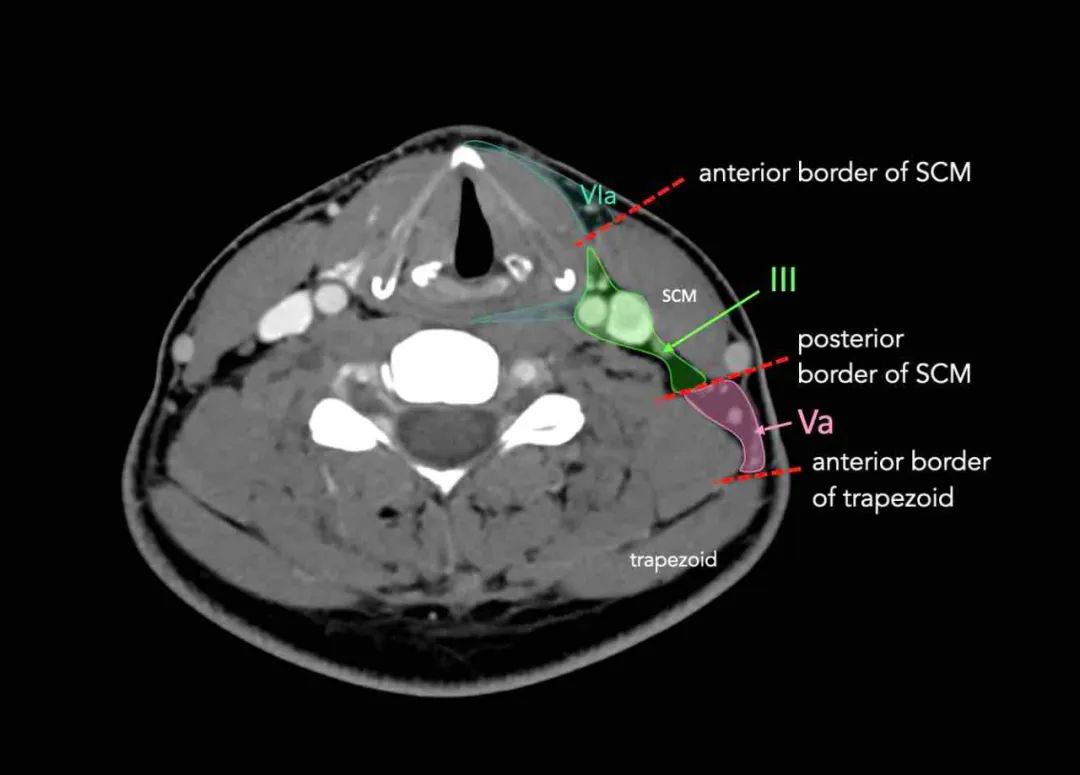

III级接受来自II级和V级的传出淋巴管,以及来自咽后、气管前和喉返淋巴结的一些传出淋巴管。

它从舌根、扁桃体、喉、下咽部和甲状腺收集淋巴管。

环状软骨的下缘是III和IVA之间的边界。

III级淋巴结有来自口腔、鼻咽、口咽、下咽和喉的癌症转移的风险。

第五层包含位于胸锁乳突肌后面,围绕着副神经和颈横血管的下部。

第五层的淋巴结通常与鼻咽、口咽、头皮后部的皮肤结构和甲状腺的原发癌有关。